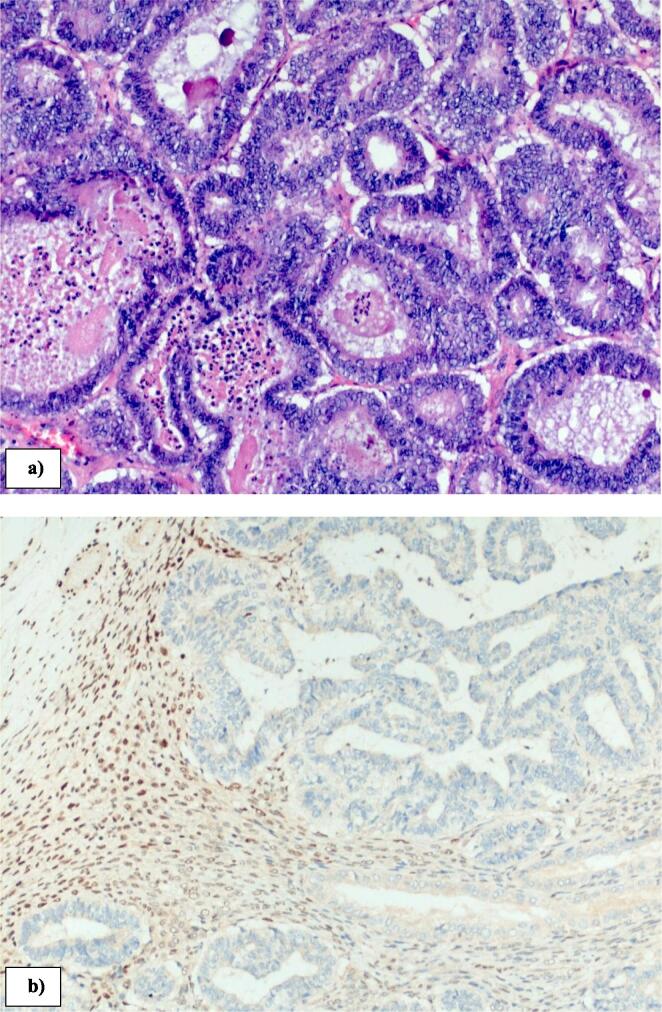

Fig. 2.

Histopathology of right ovary demonstrating a) grade 1 endometrioid adenocarcinoma (10× magnification, Haematoxylin and Eosin); b) abnormal loss of MLH1 (10× magnification immunohistochemistry).

Twelve months after initial surgery she developed right lower abdominal pain and CT scan confirmed a 5 cm multi-cystic, right adnexal mass with no evidence of distant metastatic disease. A serum Ca125 was elevated at 363 kU/L (normal range 0.00–35.0 kU/L). She subsequently underwent a laparotomy, and a large right ovarian mass (macroscopic tumour size 75 × 60 × 40 mm, weighing 76 g) (Fig. 1a) and b)) was noted to be adherent to the omentum and ileocolic bowel. She underwent a bilateral oophorectomy, omentectomy and ileocolic resection with primary anastomosis. There was no evidence of other disease at the time of surgery. Histology confirmed an adenocarcinoma (Fig. 2a) with weakly positive ER (5 %), PR weakly positive (20–30 %). There was no LVSI. Loss of MLH1 (Fig. 2b) and PMS2 was again noted. Pelvic washings were obtained for cytologic evaluation and did not show any evidence of malignancy. The pathologic features were compatible with a recurrent endometrial cancer and the patient underwent 6 cycles of combination carboplatin, paclitaxel followed by adjuvant external beam radiotherapy of 45gy in 25 fractions. The rationale for pelvic radiation therapy was for pelvic control given the high risk of recurrence for a locally advanced endometrial cancer (Creutzberg et al., 2019). She remained asymptomatic and free of disease at 12 months follow-up from her subsequent operation.